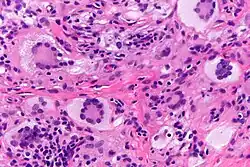

Touton giant cells in a juvenile xanthogranuloma. H&E stain.

Touton giant cells, being multinucleated giant cells, can be distinguished by the presence of several nuclei in a distinct pattern. This pattern is described as a ring-like or wreath-like in the center of a cell. These cells contain a ring of nuclei surrounding a central homogeneous cytoplasm, while foamy cytoplasm surrounds the nuclei.[6][7] The cytoplasm is usually lipid-rich and has a foamy appearance. The cytoplasm is divided into two distic areas: the peripheral zone and the central zone. The central zone is the cytoplasm surrounded by the nuclei which is described as both amphophilic and eosinophilic. Meanwhile, the cytoplasm near the periphery of the cell, the peripheral zone, is pale and contains vacuoles due to the lipid content in this zone of the cell.[1][8]